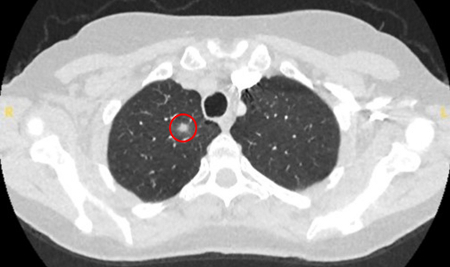

Computed tomography (CT) showing a posterior left upper lobe spiculated nodule, with ‘bronchus sign’ in a female non-smoker. Bronchoscopic forceps biopsy and brushing assisted by radial EBUS miniprobe localisation, confirmed a non-Hodgkin’s lymphoma

From the collection of Dr George Tsaknis, MD, PhD, FRCP(London), MRQA, MAcadMEd, PGCert; used with permission